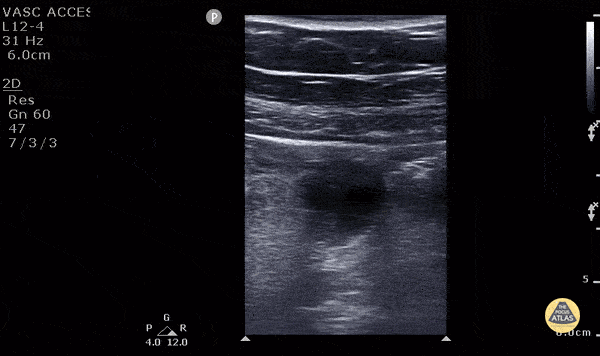

11 y/o M presented with 1 day of periumbilical pain that migrated to the right lower quadrant with nausea, vomiting and anorexia. Ultrasound with high frequency linear probe demonstrates an enlarged appendix with an external diameter of 1.32 cm with trace free fluid posteriorly, as well as a fecalith at the proximal end of the appendix. Surgery was consulted who requested a formal US which was non-diagnostic. Surgery took the patient anyway, and MRI confirmed our findings (including the large diameter). Diagnostic criteria for appendicitis: a non-compressible, aperistaltic, blind ended structure >6mm diameter. Visualizing free fluid, tenderness in that area, and visualizing a fecalith can also add to the diagnosis. See the evidence atlas for more info about POCUS diagnosing appendicitis but when visualizing a diagnostic appendicitis, it carries a positive likelihood ratio of 9.24. PMID: 28214369 Jackie Chiou MS4, Dr. Matthew Riscinti and Dr. Tian Liang - Kings County Emergency Medicine